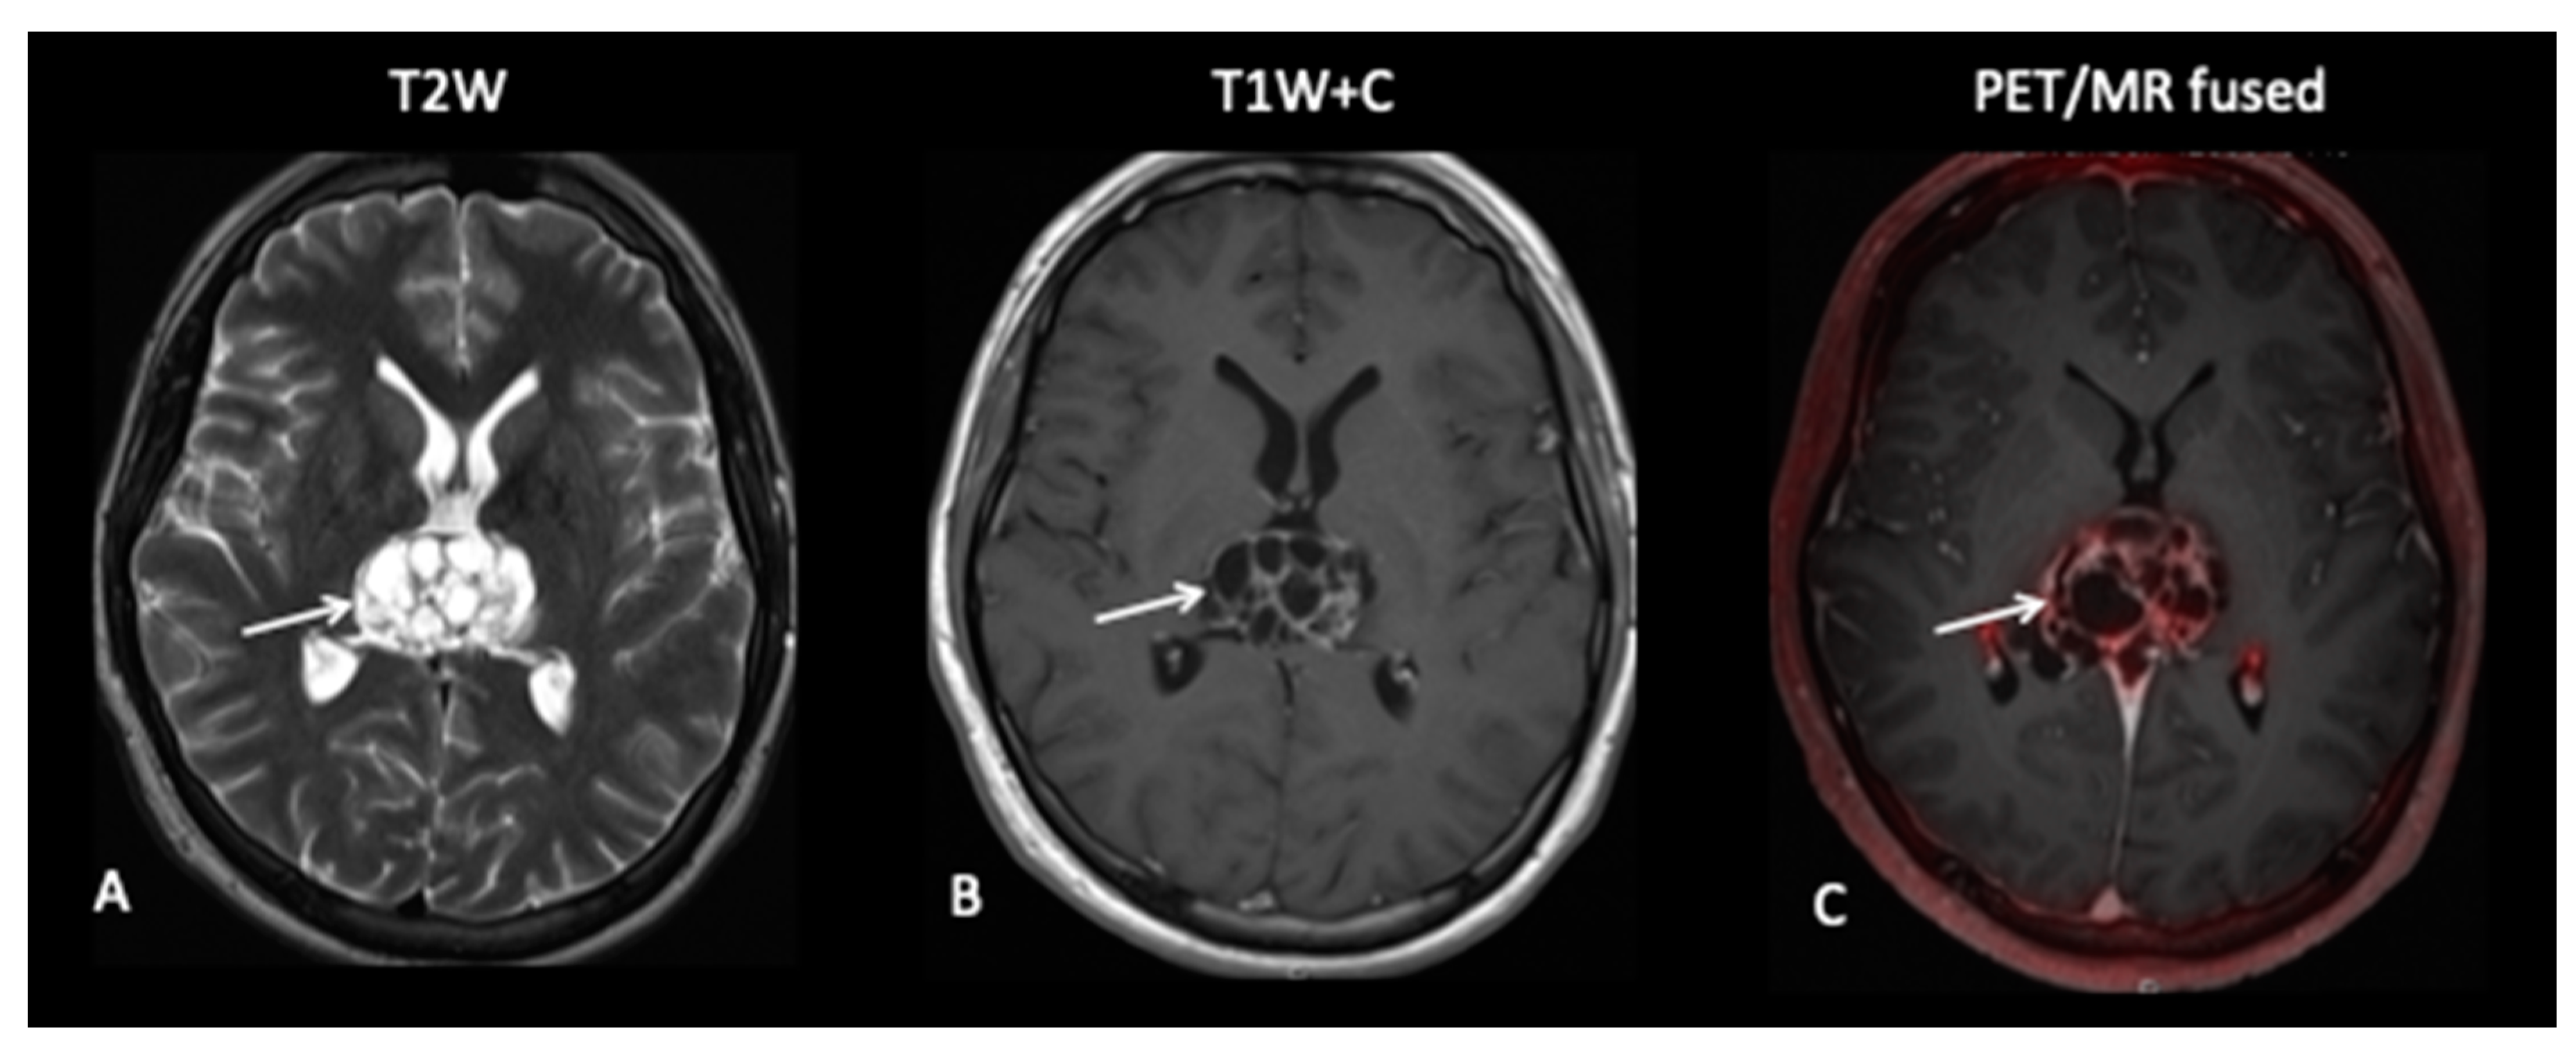

- Patient 9: Response Assessment

A 19-year-old male presented with a short history of headaches and double vision. MRI of the brain and spine showed a multi-cystic tumour pineal region tumour causing obstructive hydrocephalus. As serum AFP and bhCG were elevated, a diagnosis of intracranial NGGCT was made. After four cycles of chemotherapy, 18F-fluoroethylcholine (FEC) PET–MRI showed stable tumour volume with moderate FEC uptake, suggestive of viable tumour (Figure 12). He underwent macroscopic tumour resection that histologically showed the presence of viable tumour and subsequently proceeded to cranio-spinal radiotherapy (CSRT) with a boost to the pineal tumour.

Figure 12.

MRI demonstrated a stable residual cystic large pineal region tumour (A) with enhancement of the internal septations (B) reported as stable disease. However, 18F-fluoroethylcholine (FEC) (C) showed increased avidity consistent with metabolically active disease.